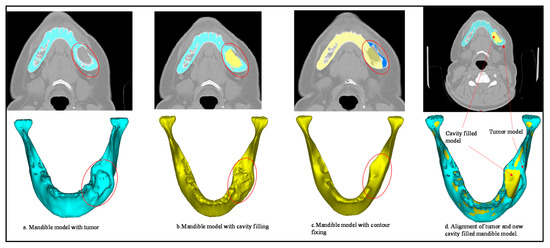

2.2. Image Acquisition and Processing

2.3. Custom Implant Design